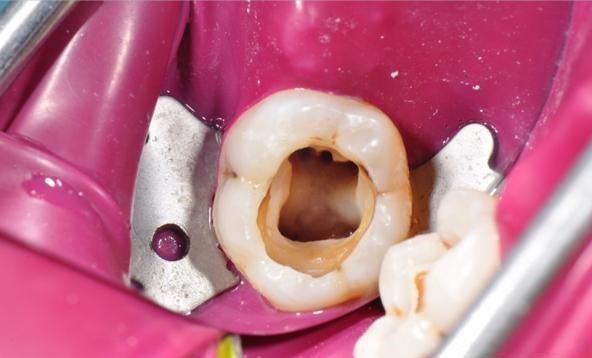

图:拔牙操作过程